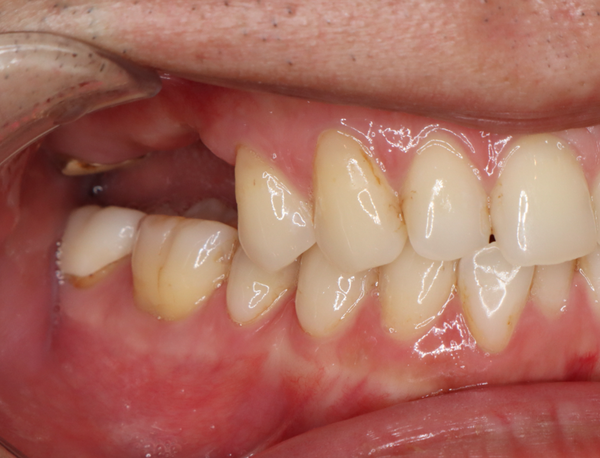

治療の経緯

右上の歯が取れたので、噛めるようにしたい

治療方法

奥歯は歯根破折していたため、抜歯をし、骨が少なかったため上顎洞にサイナスリフトを行い、骨を補填してインプラントを埋入しました。インプラントブリッジにて被せ物を作りました。

治療期間 動的期間6ヶ月

費用 インプラント埋入2本 600,000円

サイナスリフト  330,000円

セラミックのブリッジ(クラウン3本分)  450,000円

合計   1,380,000円

治療によるリスク インプラントは歯周病に弱いため、歯周病にかかると悪化する可能性があります